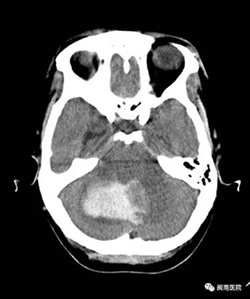

2017年3月19日凌晨,一位50多岁的王阿姨突发眩晕,意识障碍,送到我院闽南医院,急查CT确诊为小脑出血,血量达30ml,血压高达210/120mmHg,如不尽快做手术,病人将危在 旦夕!然而,据家属描述,病人还有脑梗塞病史,手术的话病人则很可能在手术台上发生危险!

众所周知,心脑血管疾病是威胁人类健康的头号杀手,而出血性中风是其中的一大类型疾病,它往往在情绪激动及使劲用力后诱发,因其“高死亡率和高致残率”给家庭和社 会带来沉重的负担。对待这种急重病人,在区县级医院里的一般大夫,要么选择非手术的保守治疗,要么建议转院处理,且病人家属也往往要求转院。万幸的是,当天外科值班的 医生正是我院本部神经外科副主任医师江常震大夫,作为福建省内神经外科界知名的医生,江大夫马上做出了急诊手术的决定,并告知家属急诊手术的迫切性和必要性。家属商讨 后决定留在闽南医院抢救。艺高人胆大,神经外科医疗组快速制定应对各类紧急情况的预案,随后在备血,降压及降颅压等充分的术前准备后,开始手术。

手术由江常震主刀,蔡明、杨旭耀、郭小洪医生作为助手配合手术。为防止颅压增高,脑疝形成,医疗组先给患者行“右侧脑室额角引流术”,为下一步小脑血肿清除、减压 赢得宝贵的时间。为了使患者头部在手术中保持稳定以利小脑的显露及减少小脑创伤,医疗组利用“三点”式头架固定头位,全程利用精巧的显微器械沿着颅内自然间隙进行操作 。

脑出血手术清除血肿过程中最关键的步骤是止血,此时高位波动的血压、动脉粥样硬化的血管和血肿周围水肿的脑组织给止血带来了极大的挑战,但是江大夫沉着冷静、从容 不迫,经过5个多小时的手术,病人的血肿全部清除,出血点也得到了有效控制。为做好术后围手术期管理,术后江大夫带领神经外科团队每天蹲守在重症监护室(ICU)密切观察 患者病情变化,指导管床医师处理及用药,确保病人平安度过危险期。而且,在回到普通病房后,江大夫还积指导病人做康复功能锻炼。历时近一个月,在医生的协助下,病人终 于战胜了病魔,痊愈出院。病人及家属对治疗效果非常满意,并为江大夫的精湛技术点赞。因江常震大夫是神经外科专家,大家私底下亲切地称他为“江神医”。

据江常震介绍,小脑手术的风险在于:一是周围有大血管,静脉窦,稍有不慎,可能造成大出血危及生命,而一旦损伤,血管难以修复,不像其他血管一样可以结扎修复;二 是小脑深部贴近脑桥和延髓等生命中枢,稍不留神就可能出现呼吸、心跳骤停!开颅规范是手术成功的基础,小心解剖是成功的关键,因此手术必须在手术显微镜下进行才能提高 成功率,因为显微镜能够放大局部病灶,有立体感。